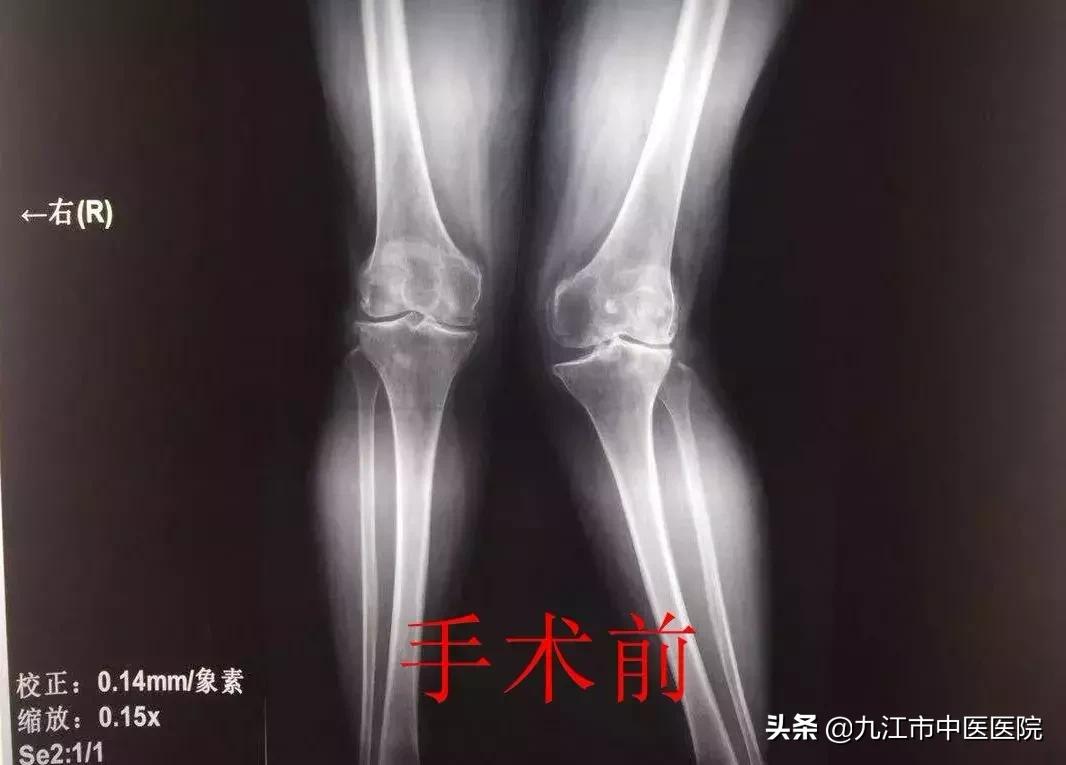

接诊后,王毅带领团队详细分析了该患者相关病史、体征,并行相关影像学检查,经检查发现,该患者为重度膝外翻畸形(股胫角>20°),手术难度较大、风险高。

在和家属充分沟通并取得同意后,经过术前反复论证,最终选择采用适当的截骨与松解技术,根据患者关节稳定程度选择了稳定型膝关节假体。手术非常顺利,术后患者膝关节疼痛减轻,膝外翻畸形纠正,72小时后即可在家人搀扶下下地行走,无任何神经受累症状,目前已恢复正常生活自理活动,正在康复中。